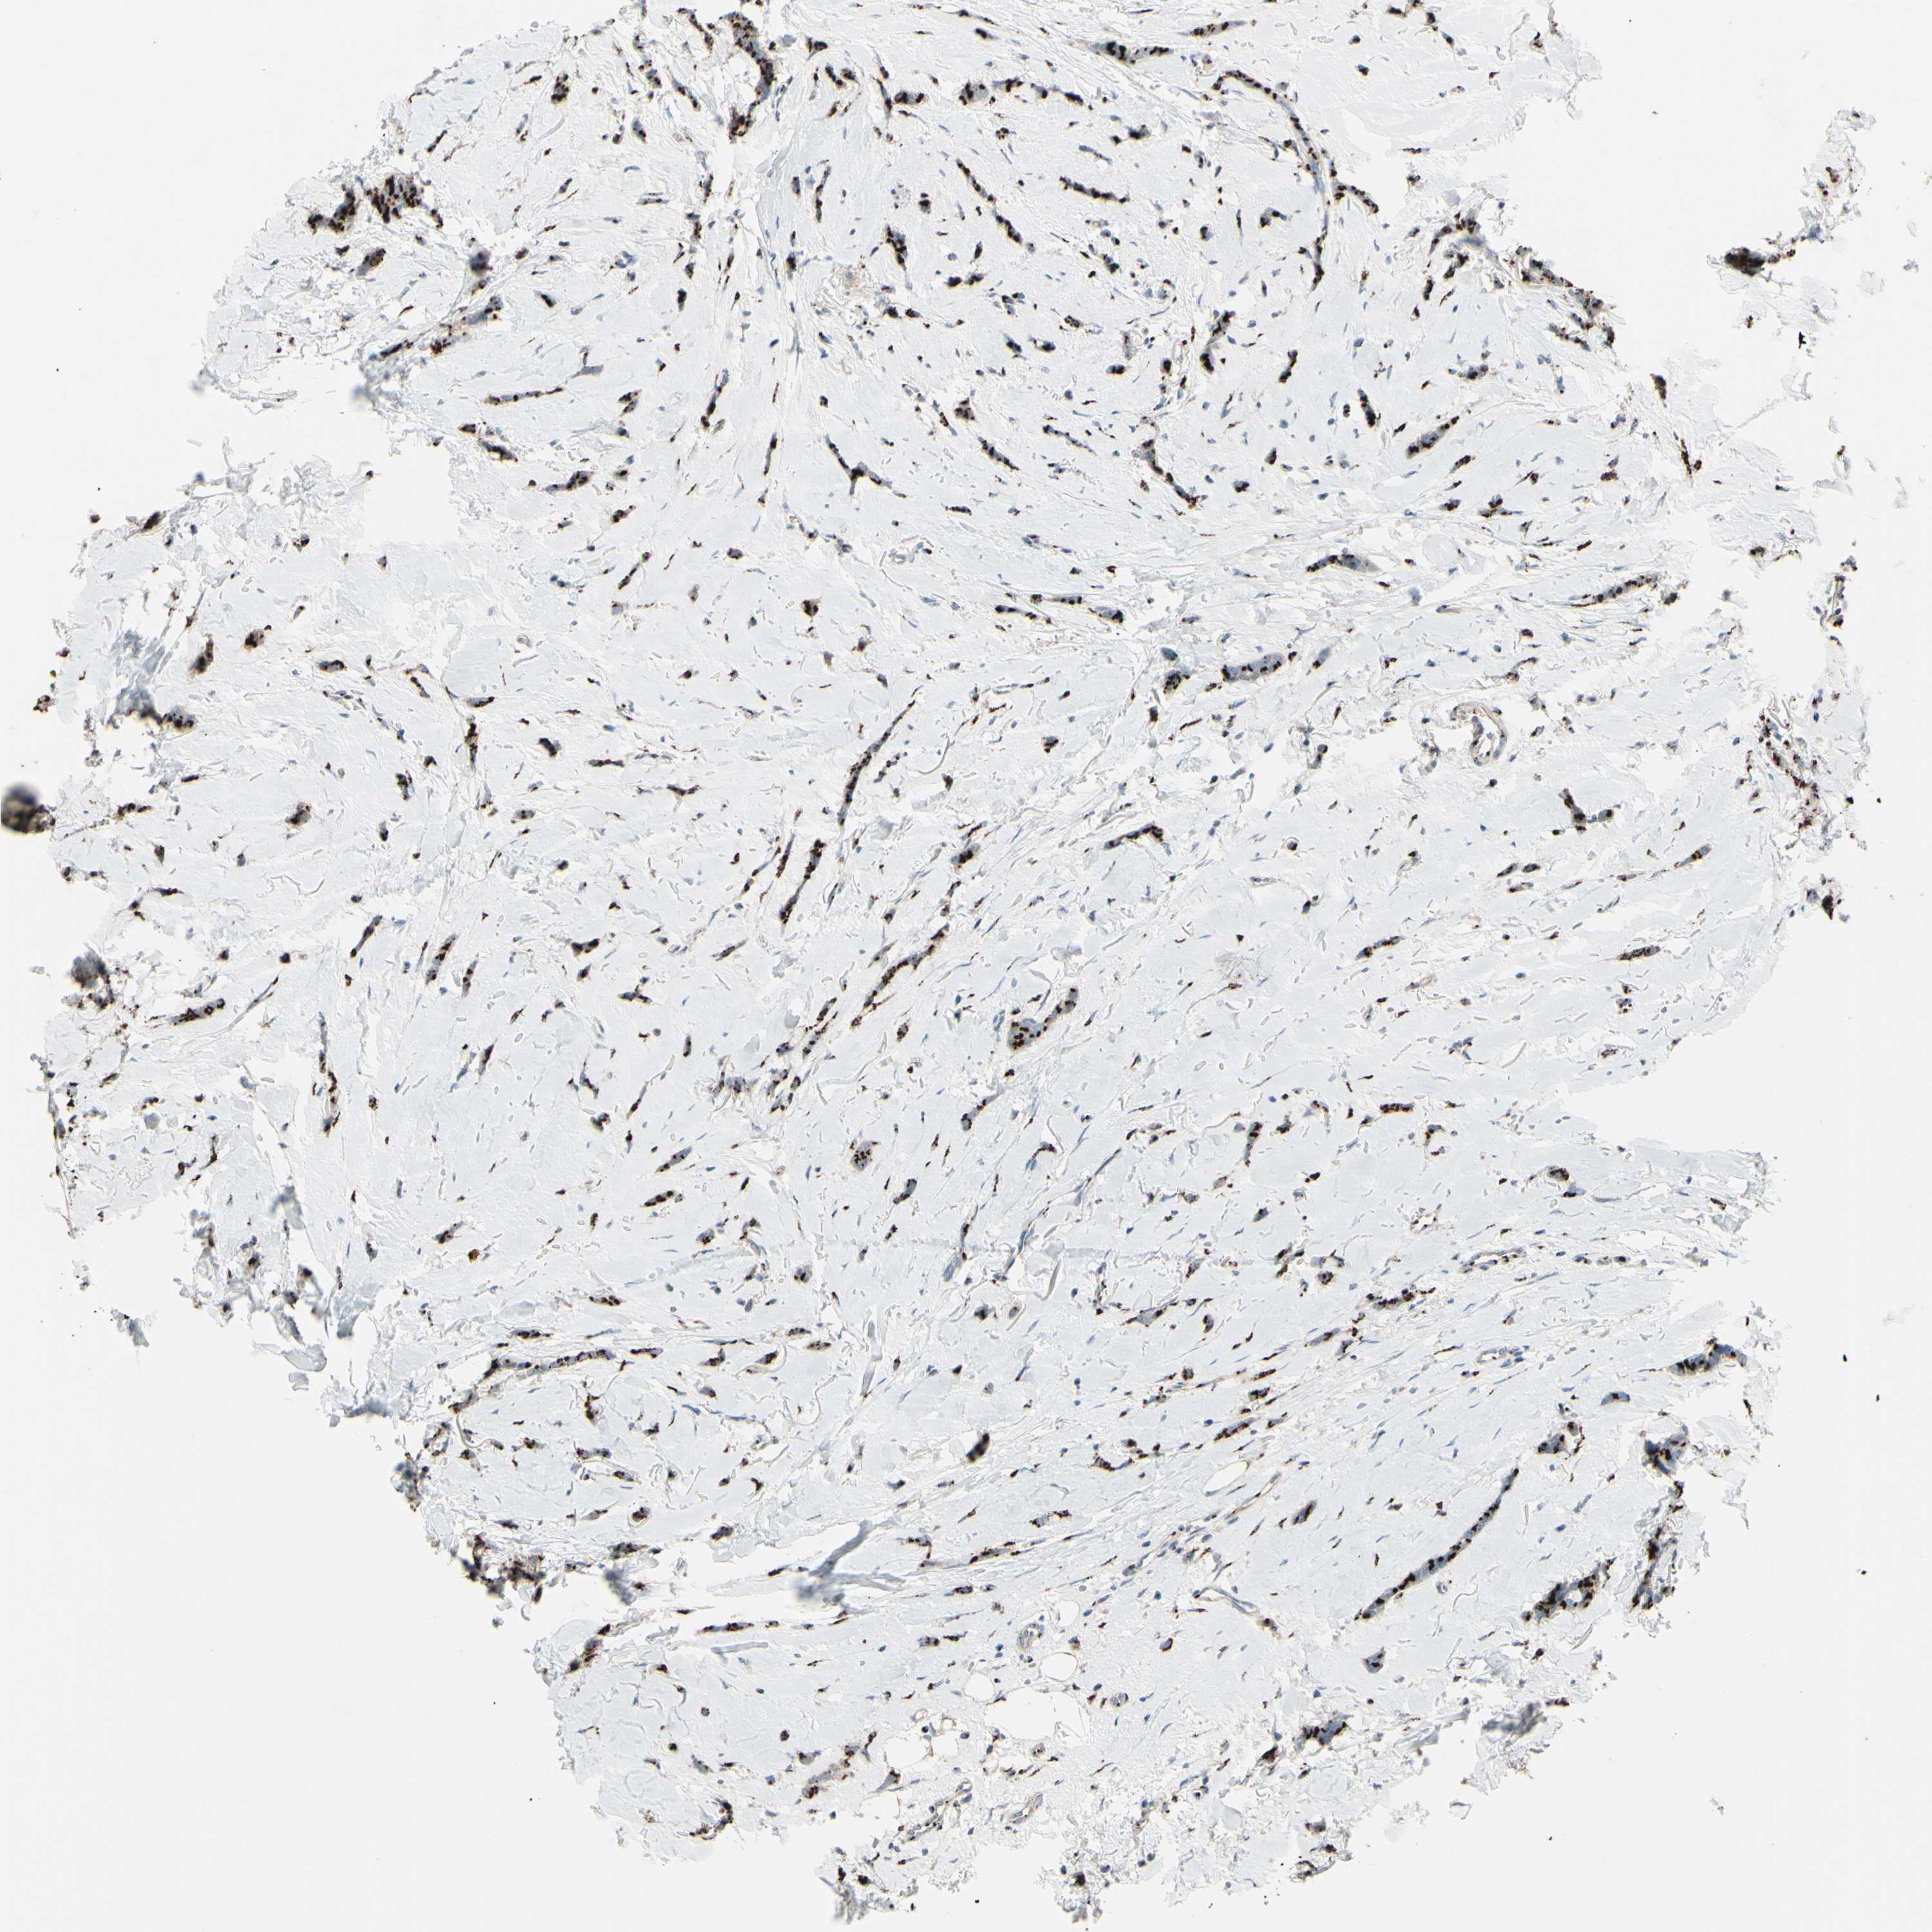

BRCA TCGA BRCA VALIDATION PROTEIN EXPRESSION

ANTIBODIES

AND

VALIDATION